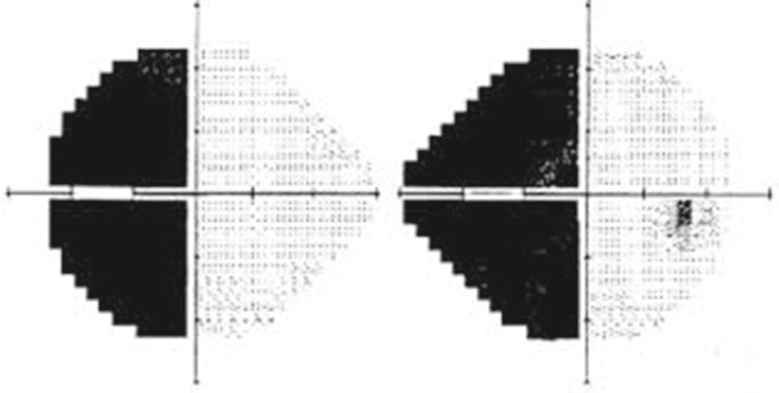

Devant une hémianopsie (fig. 8.20) ou une quadranopsie latérale homonyme (fig. 8.21) par atteinte des voies optiques rétrochiasmatiques, l’installation brutale évoque une étiologie vas- culaire, alors qu’une installation progressive évoque une étiologie tumorale.

Diagramme en niveaux de gris issu d’un champ visuel Humphrey, révélant une hémianopsie bitemporale typique. Chaque moitié du visuel correspond respectivement à l’œil droit et à l’œil gauche, séparés par une ligne verticale centrale. Dans les deux cas, les moitiés temporales, c’est-à-dire les zones latérales de chaque œil, apparaissent complètement noircies, signe d’une perte de champ visuel bien délimitée. Cette disparition symétrique des champs temporaux, parfaitement respectueuse de la ligne médiane verticale, évoque très directement une atteinte au niveau du chiasma optique, généralement provoquée par une compression, comme celle engendrée par un adénome hypophysaire. À l’inverse, les champs nasaux restent intacts et montrent des plages claires traduisant une sensibilité visuelle préservée. L’image met donc en évidence un déficit précis, bilatéral et topographiquement chiasmatique, sans aucune ambiguïté.

Cette image correspond à un champ visuel réalisé avec la méthode automatisée Humphrey, illustrant de façon nette une hémianopsie latérale homonyme gauche. On y observe, pour les deux yeux, une perte de sensibilité complète dans l’hémichamp gauche de chaque rétine, matérialisée ici par des zones noircies en miroir. Cette atteinte typique traduit une lésion rétrochiasmatique, vraisemblablement localisée au niveau du tractus optique droit, du corps genouillé latéral droit, des radiations optiques ou du cortex visuel occipital droit. L’aspect régulier et symétrique de la perte dans les deux hémichamps temporaux des yeux met en évidence le caractère neurologique de l’atteinte, souvent associée à des AVC, des tumeurs cérébrales ou des traumatismes. Ce type de visuel n’est pas une simple photo, mais un rendu cartographique des réponses sensorielles du patient, utilisé en neuro-ophtalmologie pour préciser la topographie des lésions visuelles centrales.